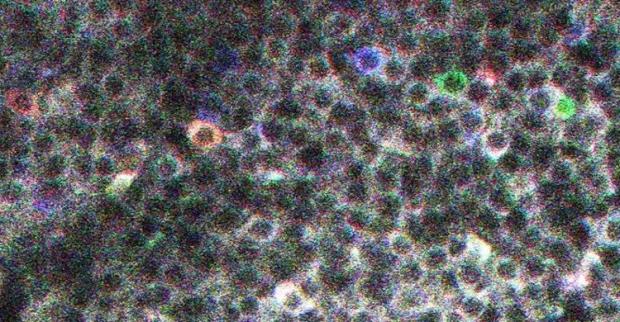

Một nhóm các nhà nghiên cứu thuộc Viện thần kinh học Méditerranée ở Pháp đã phát hiện ra các tế bào kí ức bằng cách tiêm một loại protein huỳnh quang vào tế bào thần kinh của bốn con chuột. Loại protein đặc biệt này sẽ sáng lên khi tiếp xúc với ion canxi tiết ra từ tế bào thần kinh. Đây là một dấu hiệu chắc chắn cho thấy rằng các tế bào thần kinh đang hoạt động.

Khi cho những con chuột chạy trên máy chạy bộ, các tế bào thần kinh kí ức bắt đầu sáng lên và hoạt động tích cực nếu quá trình chạy lặp lại liên tục. Điều này cho thấy, những tế bào đã thu thập thông tin và lưu lại vào kí ức. Khi những con chuột này nghỉ ngơi, các tế bào cũng hoạt động nhưng mờ đi nhanh chóng. Hình dạng và màu sắc của các khối tế bào ký ức cũng trở nên khác biệt so với khi những con chuột đang chạy.

Những tế bào não phát ra ánh sáng khác nhau cho từng loại kí ức khác nhau. (Nguồn ảnh: Viện thần kinh học Méditerranée).